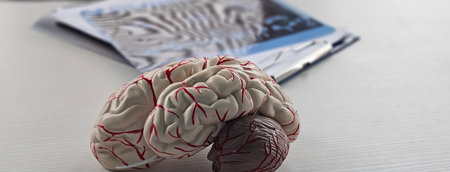

This image features a detailed human brain model, showcasing the vascular structure, set in a modern laboratory environment, ideal for educational materials.

This high-quality image features an anatomically accurate brain model, showcasing intricate vascular structures and the spinal cord, ideal for educational use.